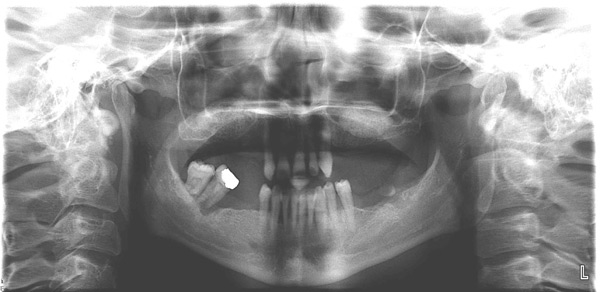

Problem: This patient presented with severe decay and a difficult occlusion/bite. He had teeth that had already been removed.

Plan: Our plan… remove the rest of the teeth and place an upper denture. Place four implants on the lower using guided surgery. Restore with a fixed/hybrid bridge.

A solution to every problem.